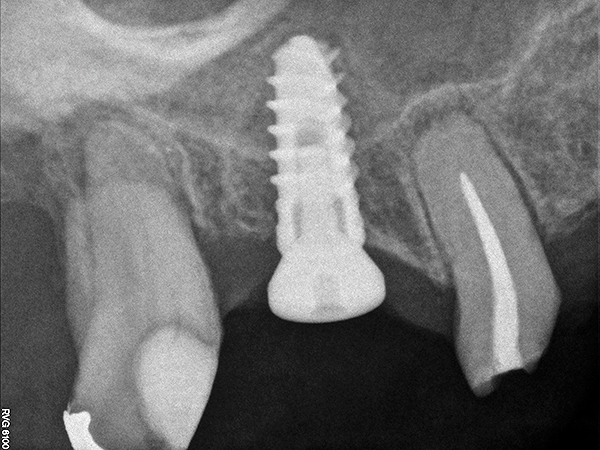

As with implant placement in general, use of a round bur is the first step in forming the osteotomy. As described above, to get verification of positioning—especially if a surgical stent is not used—a small piece of gutta percha can be placed inside this small osteotomy and a radiograph taken (Figure 1), after which the gutta percha is removed. The next step is the most critical, as it involves exposing the Schneiderian membrane. A 2-mm twist drill is used at a speed not exceeding 250 rpm, using a very light touch. Because the bone quality in the maxillary posterior is generally poor, it is usually easy to feel when the medullary bone has been breached and the dense cortical bone of the floor of the sinus has been reached. The cortical plate of the floor of the sinus should have been carefully measured with periapical radiographs presurgically, but it is usually about 1 mm in thickness. The most important and technique-sensitive part of this procedure is breaching the cortical plate of bone lining the sinus without tearing the sinus membrane. With a solid finger rest, good control, very light drilling pressure, copious irrigation, and a slow drilling speed, a slight “give” occurs once this plate of bone is breached. The full width of the twist drill should not penetrate the sinus floor; otherwise, the membrane will be torn. If it is not clear whether the membrane has been exposed, a flat-ended implant probe (Figure 2) can be used by inserting it into the osteotomy and feeling for the slight “give” or movement of the membrane. If the surgeon is not sure if the membrane is exposed, a radiographic marker can be used (Figure 3). If the membrane is significantly exposed, however, a radiographic marker should not be used, as this can inadvertently tear the membrane. The patient should also be warned not to bite down on the marker during the radiograph to avoid a membrane tear, and floss must be attached to the marker, so it can be retrieved if necessary.

Fig 1. Radiograph of gutta percha placed at the base of the initial osteotomy with a round bur to verify location.

Figure 1